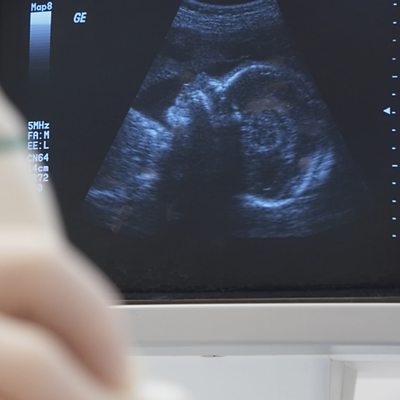

Joan Bakewell speaks to disability campaigner Kaliya Franklin, fertility expert Alison Murdoch and ethicist Deborah Bowman to discuss the ethics in the case of Rosemary, who has Ehlers-Danlos syndrome and is seeking assisted conception despite the risks it poses to her life. Kaliya argues that disabled people have a very different appreciation of risk, especially from clinicians, because of the ever-present risks they live with every day.